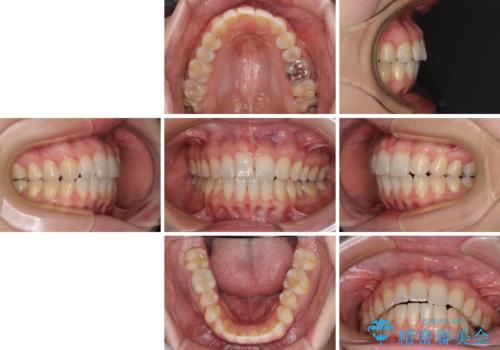

- 矯正治療の後戻りが気になるとのことで来院された患者様です。

上顎の後戻りをインビザライン・ライトで治療することとしました。

上顎のみの治療を希望されたため、咬み合わせをしっかりと改善することはできませんでしたが、審美面が大きく改善され、日常生活の機能面でも不具合を感じることはなく、大変満足していただきました。